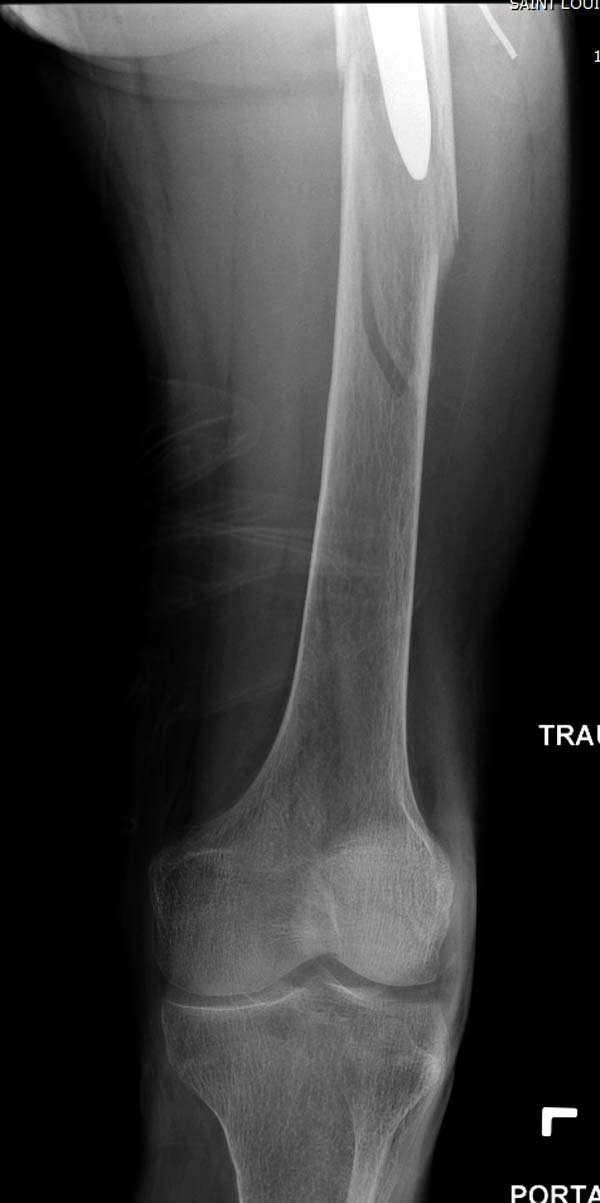

Больному 25 лет, транспортная травма. С детства хроническая почечная

недостаточность, постоянный гемодиализ, находится в листе ожидания на

пересадку почки. Около 4 года назад автоавария с двухсторенним переломом

ацетабулум, которая слева закончилось тотальным протезированием.

Диагноз: переломы бедренных костей, перелом дистального плеча слева,

также неосложненный перелом на уровне грудных позвонков.

Имя     : 5 Periprosthetic IM nail Lt femur 3.jpg